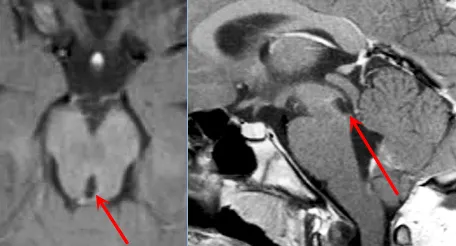

术后影像学复查结果

手术几天后按计划进行,巴教授团队经过数小时精心操作成功切除肿瘤。术后病理检查显示为WHO Ⅲ级间变性星形细胞瘤(Anaplastic Astrocytoma)。通过巴教授15年长期随访,马修现已顺利进入成年阶段。尽管童年时期遭遇重大疾病,但成功的手术治疗为他争取了完整的少年和青年时期。目睹目前笑容满面、精神饱满的马修,父母深感庆幸当年的治疗选择不仅避免严重后遗症,更挽救了他的生命。术后影像学检查结果显示良好。